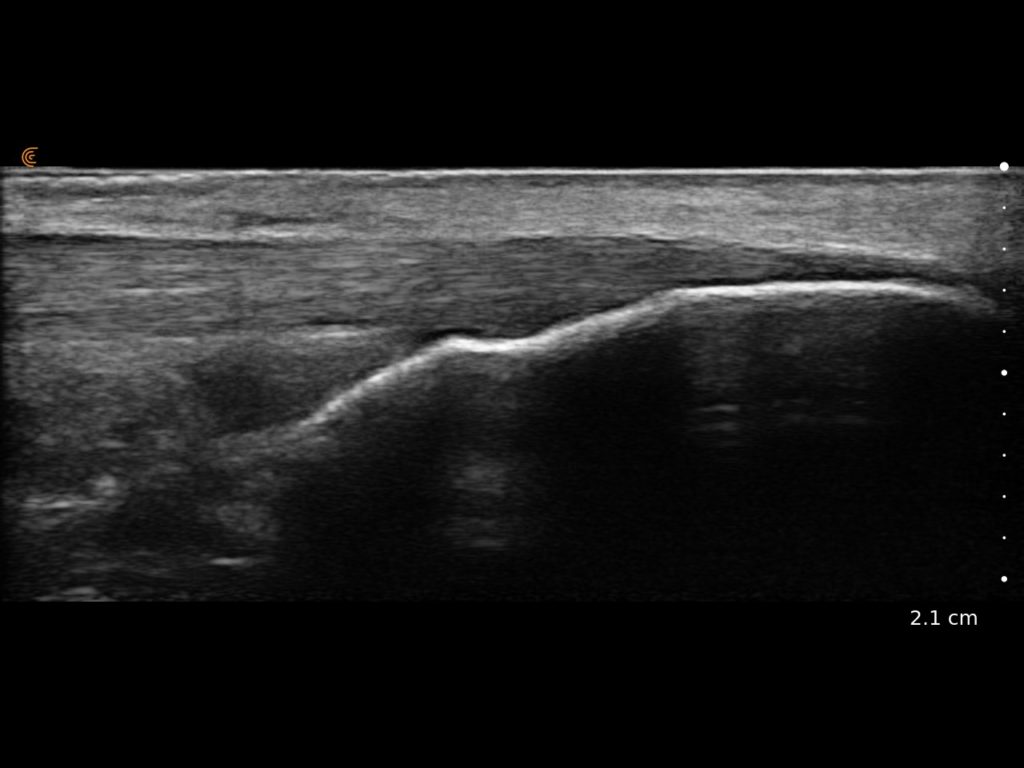

Elevate your sports medicine practice with high-definition dynamic imaging of muscles, joints, and tendons for accurate diagnostics and guided interventions on and off the field.

You can carry it from office to office, put it in your lab coat and use it on pain rounds. The image quality is superior.